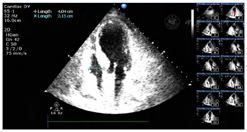

患者,女性,84岁,因"反复胸痛1周,持续加重8 h"于2021年8月17日急诊收治入院。既往无高血压、糖尿病病史。入院查体:血压105/56 mmHg(1 mmHg=0.133 kPa),神清,气略促,对答切题,颈软,颈静脉无怒张,双肺呼吸音粗可闻及较多的湿啰音,心率112次/min,律齐,各瓣膜区未闻及病理性杂音,腹平软,无压痛,反跳痛,肝脾肋下未及。双下肢轻度浮肿,四肢肌力正常,病理征(-);急诊心电图示:急性广泛前壁心肌梗死(图1);胸部CT提示双侧间质性肺水肿可能(图2);实验室检查:肌钙蛋白T:3.13 μg/L,肌酸激酶同工酶:188.93 μg/L,D二聚体:1.36 mg/L。根据患者病史、心电图及心肌酶学明确诊断为急性ST抬高型心肌梗死,予以术前嚼服负荷量绿色通道行急诊再灌注治疗,冠脉造影示:前降支次全闭塞,远端TIMI血流0级,回旋支近端40%~50%局限性狭窄,TIMI血流3级,右冠起源左冠窦,无狭窄,TIMI血流3级,于前降支近端植入3.0 mm×18 mm Firebird 2支架一枚(附件冠脉造影+PCI图3、视频1)后安返CCU。继续予以心电及血流动力学监测,动态监测心电图及酶学改变,阿司匹林、替格瑞洛抗血小板聚集,他汀调脂、稳定斑块,扩管利尿改善心功能等治疗。3 h后患者突发血压下降为60/40 mmHg,四肢湿冷,动脉搏动弱,意识尚清,指末氧饱和度95%,心电监测提示窦性心动过速,心率130次/min。立即予以平衡液扩容,多巴胺+去甲肾上腺素提升血压,留置颈内静脉置管监测CVP,股动脉置管监测有创动脉压。床旁心超提示微量心包积液,右房室内径偏小(37 mm×18 mm,40 mm×22 mm),左室壁多壁段运动异常,EF35%(图4),床位医师考虑容量不足,继续补液扩容及血管活性药物升压,但患者血压仍未见回升;再次复查心超提示心包积液较前明显增多,未见室壁不连续及异常血流信号,考虑心包填塞(图5),立即行心超定位剑突下心包穿刺,引流出暗红色不凝血,予以心包置管留置引流出血性液体300 ml,患者血压恢复至119/49 mmHg,心率95次/min,再次复查心超示左室心尖处见几束细丝状异常血流信号局限于纤维膜状回声内,考虑左室心尖破裂伴假性室壁瘤可能性大(图6)

出院前复查心超:左室壁破裂修补术后,左室壁节段性运动异常伴心尖部室壁瘤形成,EF34%,微量心包积液(图7)。